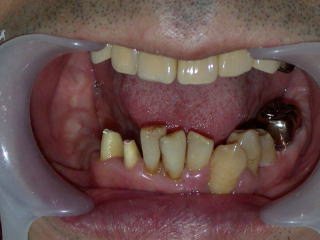

保険内診療で歯石を取り、保存不可能な歯を抜歯し、詰め物、かぶせ物も終わりました。

約半年後の平成20年2月、右下に入れ歯を作るところまで診療が進みました。